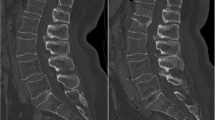

Vertebral fractures were determined from radiographs taken at baseline (M0) and annually thereafter. Radiographs were analyzed semi-quantitatively [19], with a new vertebral fracture defined as a change from grade 0 to grade 1 or higher [19]. Clinical vertebral fractures were defined as new or worsening fractures with back pain and/or body height loss of ≥1 cm. Radiographs were assessed centrally (CEMO, France; Pr C. Roux).

Four-year treatment period

The risk of new vertebral fracture over the M0 to M48 period was reduced by 33% with strontium ranelate, relative to placebo [risk reduction (RR), 0.67; 95% CI (0.55, 0.81), p < 0.001]. The number of patients needed to treat for 4 years to prevent one new vertebral fracture was 11 [95% CI (7, 24)]. Among severely affected patients (with two or more prevalent vertebral fractures at baseline), risk reduction with strontium ranelate was 36% (RR, 0.64; 95% CI (0.50, 0.81), p < 0.001]. The total number of new vertebral fractures was significantly lower in the strontium ranelate group (275) than in the placebo group (421; p < 0.001). The risk of new clinical vertebral fracture was reduced by 36% with strontium ranelate relative to placebo [RR, 0.64; 95% CI (0.49, 0.83), p < 0.001] (Fig. 2).